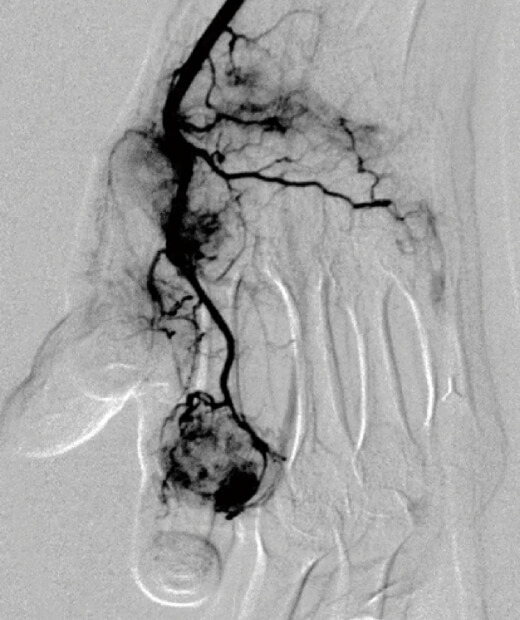

提供元:Okuno Clinic. 奥野 祐次医師

モヤモヤ血管とは、痛みの原因となる部位に新たにできてしまう「異常な血管」のことを指します。

人間の体には本来、生命維持のための「正常な血管」が張り巡らされていますが、病気や慢性的な炎症などによって、通常とは異なる構造の血管が作られてしまうことがあると近年わかってきました。

これらの異常血管は、細く枝分かれしながら増殖し、画像上で“モヤモヤ”と見える形から 「モヤモヤ血管」 と呼ばれています。